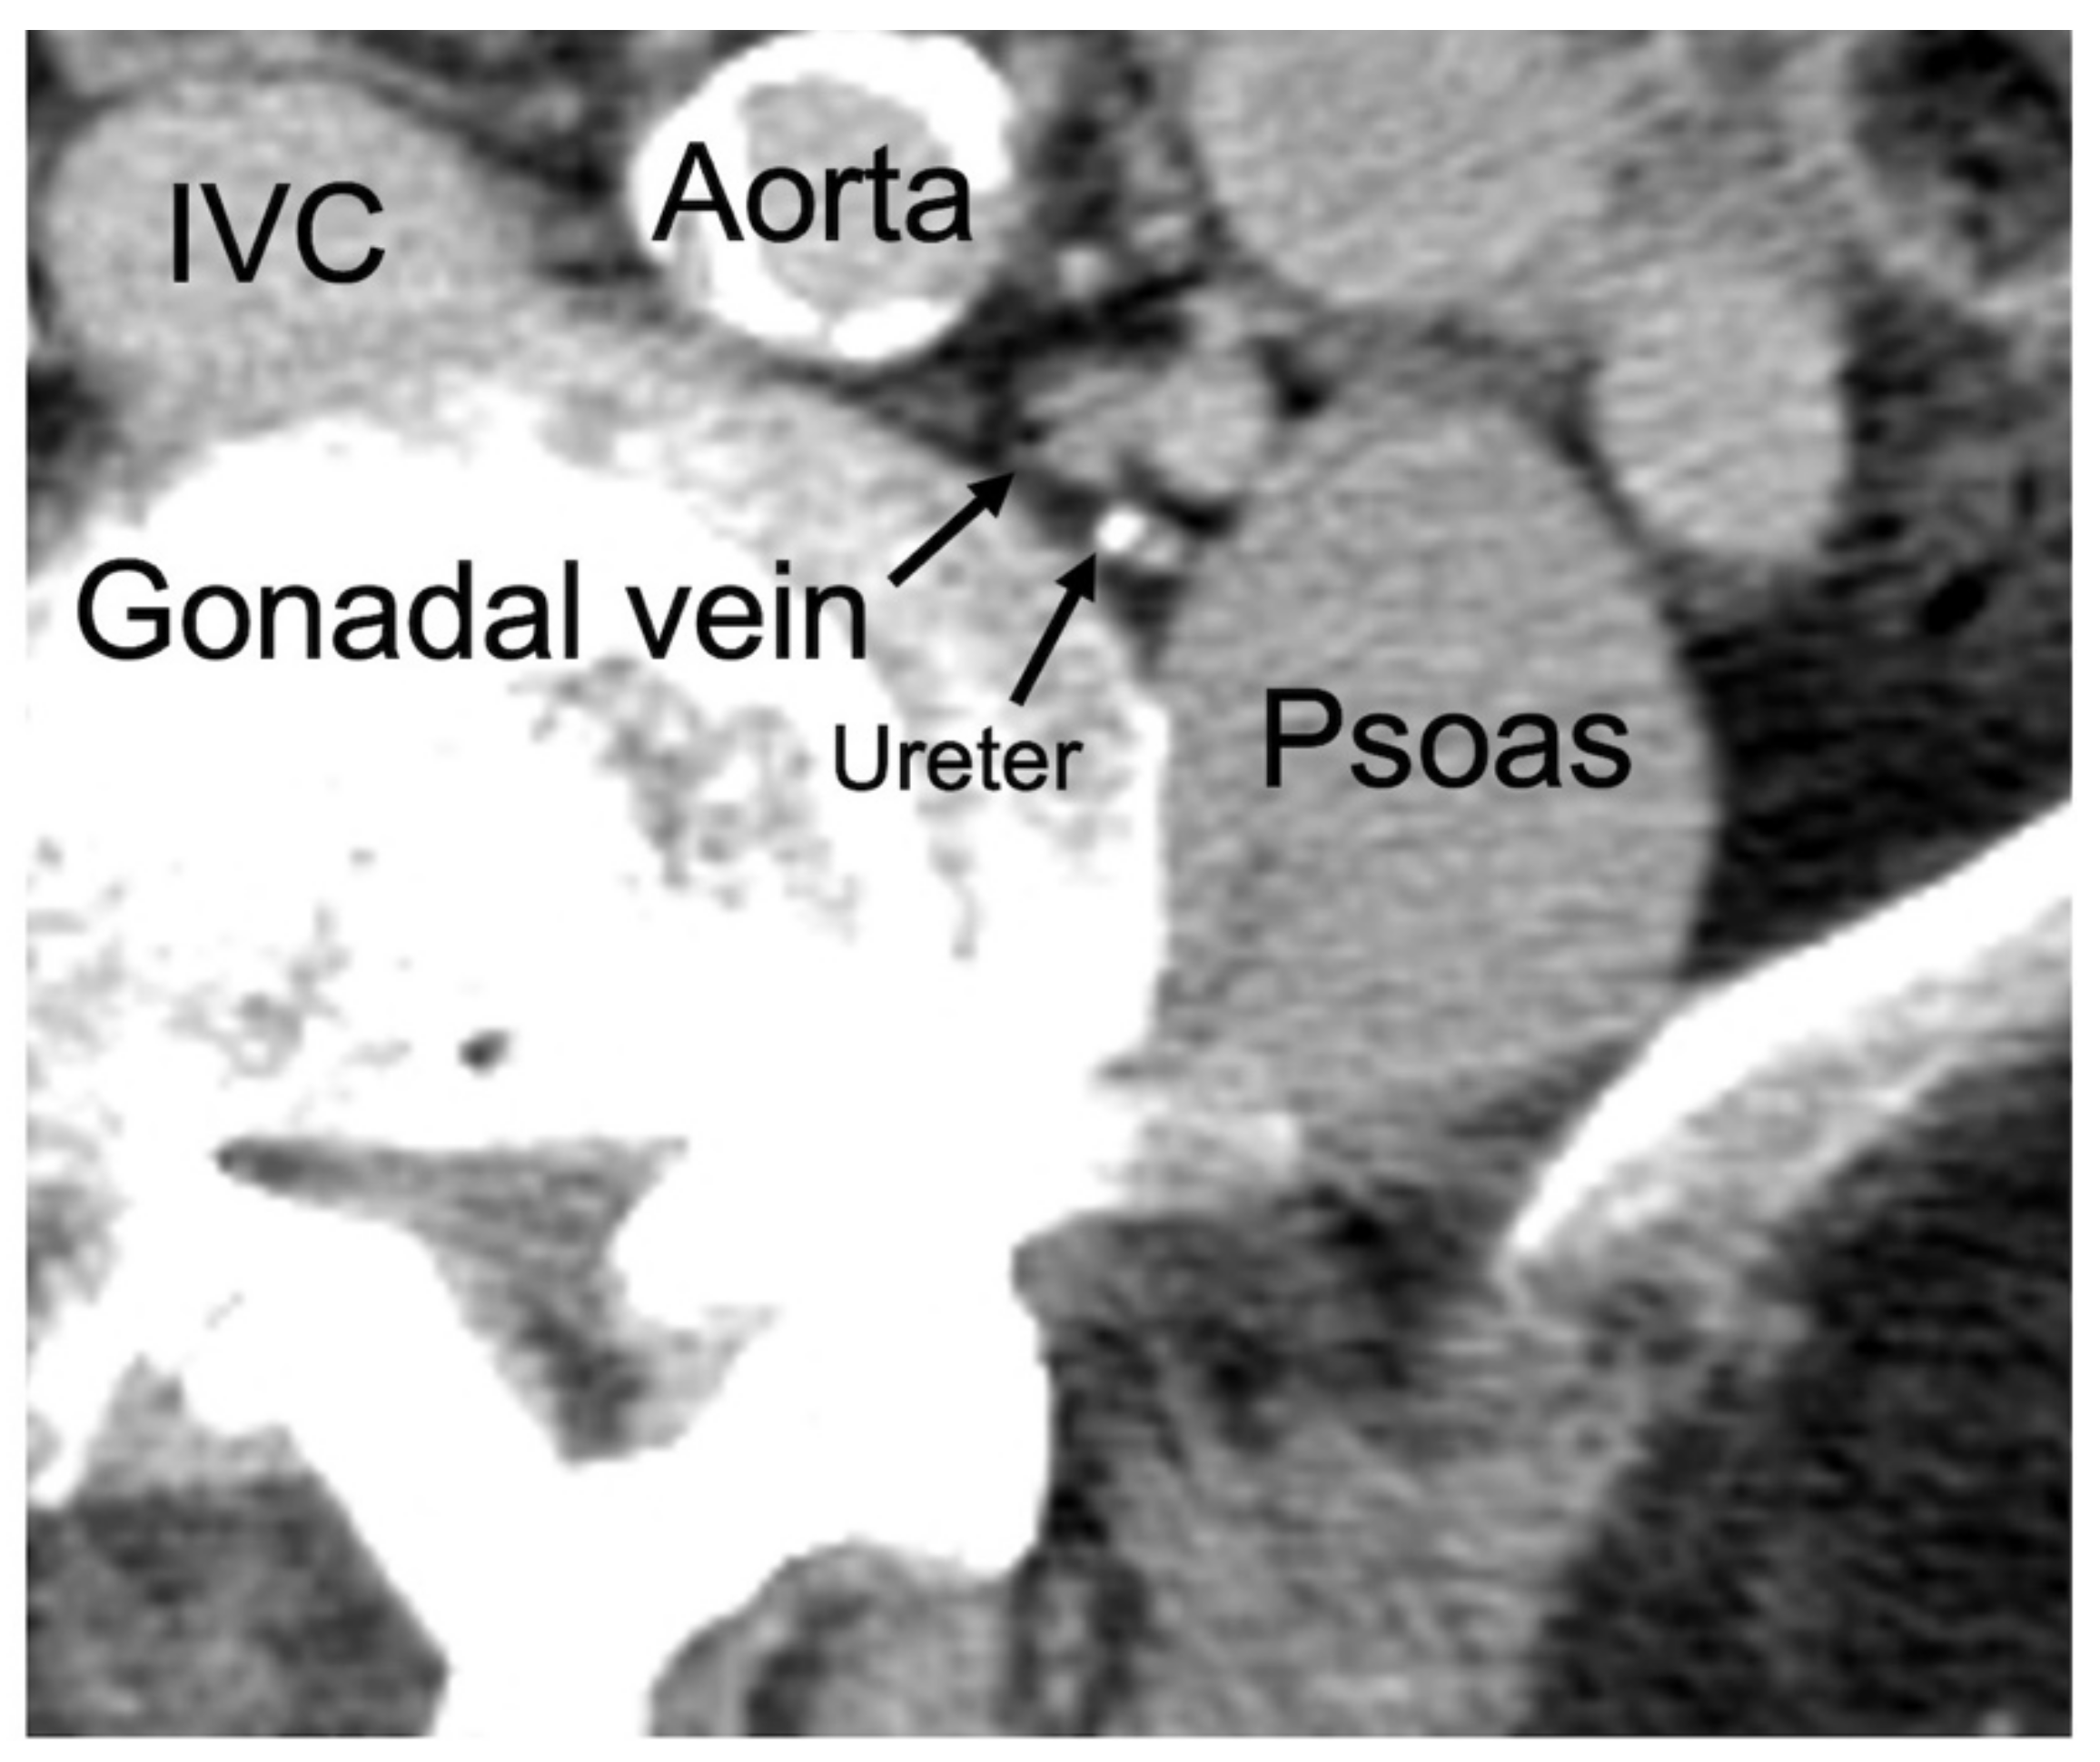

2.2. Classification of GV Location

2.3. Patients with GV in the DM Region